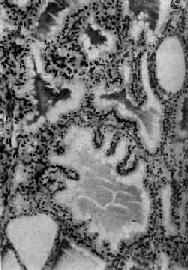

肉眼观,甲状腺对称性弥漫肿大,一般为正常的2~4倍,质较软,切面灰红,胶质含量少。镜下,以滤泡增生为主要特征,滤泡大小不等,以小型滤泡为主。小型滤泡上皮呈立方形,大型滤泡上皮多为高柱状,常向腔内形成乳头状突起。滤泡腔内胶质少而稀薄,胶质的周边部即靠近上皮处出现大小不等的空泡,有的滤泡内甚至不见胶质。间质中血管丰富,显著充血,有多量淋巴细胞浸润并有淋巴滤泡形成(图15-7)。经碘治疗的病例,由于碘能阻断含甲状腺素胶质的分解和促进胶质的储存,故胶质增多变浓,上皮增生受抑制,间质充血减轻,淋巴细胞也减少。与此相反,经硫脲嘧啶等阻断甲状腺素合成的药物治疗者,由于血中TSH代偿性增加,故滤泡增生更明显,上皮呈高柱状,胶质更稀少甚至消失。

图15-7 毒性甲状腺肿

滤泡增生,有的扩大,上皮呈立方或高柱状,并乳头状突起。滤泡腔内胶质稀薄,周边有大小不等空泡